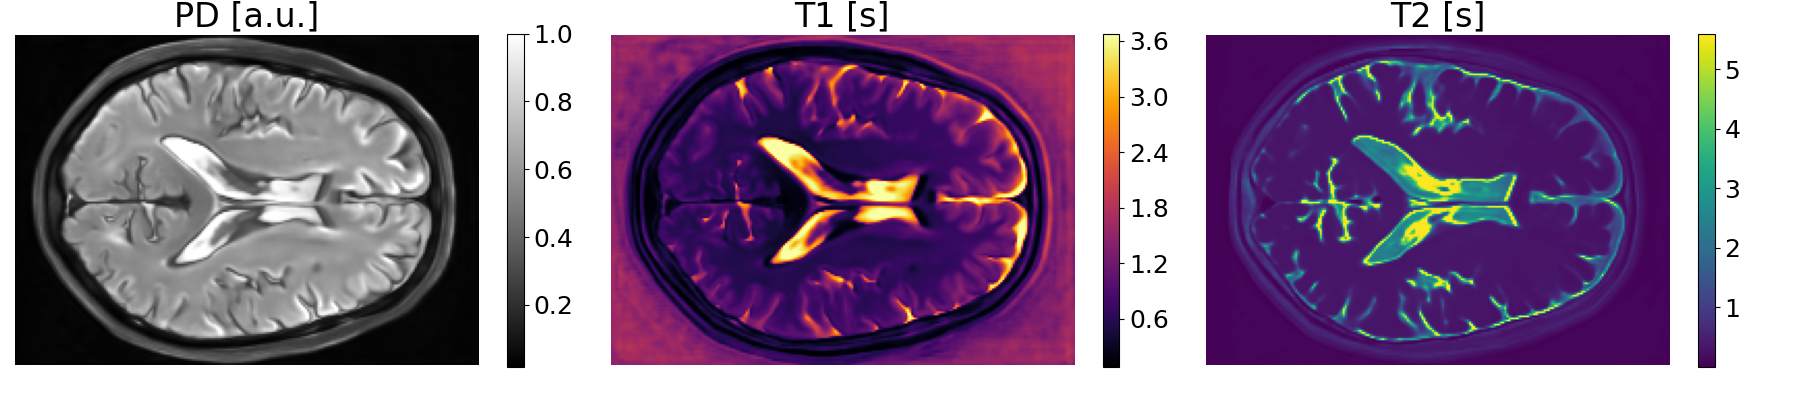

In this paper, we propose a novel physics-informed diffusion-based generative model for multimodal brain MR scans. Inspired by quantitative MRI techniques [13, 12], we utilize the acquisition parameters [6] in combination with a physical signal model [2] and a latent diffusion model to synthesize images in a two-step process: (1) The generation of modality shared physical tissue property maps, namely the proton density, the longitudinal relaxation time, and the transverse relaxation time, (2) The application of a physical signal model with a desired set of scanner acquisition parameters to the tissue property maps to obtain the final MRI scan.

The signal intensity in an MRI scan is mainly influenced by two factors: the scanner configuration and the tissue properties. Given the tissue properties, an MRI simulator can generate a variety of MR contrasts based on the chosen MR sequence and the acquisition parameters. However, due to the high computational cost of a full MRI simulation, the relationship between tissue properties, which are given by the proton density (PD), the longitudinal relaxation time (T1) and the transverse relaxation time (T2), and the signal intensity is instead modeled by a set of signal equations. These equations only depend on a subset of all possible acquisition parameters, namely the echo time (TE), the repetition time (TR), and the inversion time (TI). For T1-weighted MPRAGE [5], T2-weighted spin-echo (SE) [8] and FLAIR [8] sequences, the equations modeling the signal intensity at a spatial location are given by:

The tissue properties T1, T2, and PD depend on the location , whereas is a global parameter that models the scanner gain. Our model ignores the scanner gain and assumes . Since the signal depends linearly on PD and G, any scanner-specific signal scaling is absorbed into the proton density map.

To efficiently perform denoising diffusion to generate tissue property maps containing PD, T1, and T2, we design a multimodal physics-informed variational autoencoder that downsamples multimodal MRI scans by a factor of 8 into a shared lower dimensional latent representation.

We decode the shared latent representation using a convolutional network into tissue property maps by passing its output through the exponential function, ensuring that the property values are greater than zero, and transforming the resulting values by the signal model (Equation 1) to reconstruct the input. Following previous work [20, 18], we combine an L2 reconstruction loss with a perceptual loss, a patch-wise adversarial loss, and a KL-regularization loss on the latent distribution.

We set and based on the median of the property value distribution measured in real brain tissue [1], corresponding to a log-normal prior with a median of on T1 and a median of on T2.